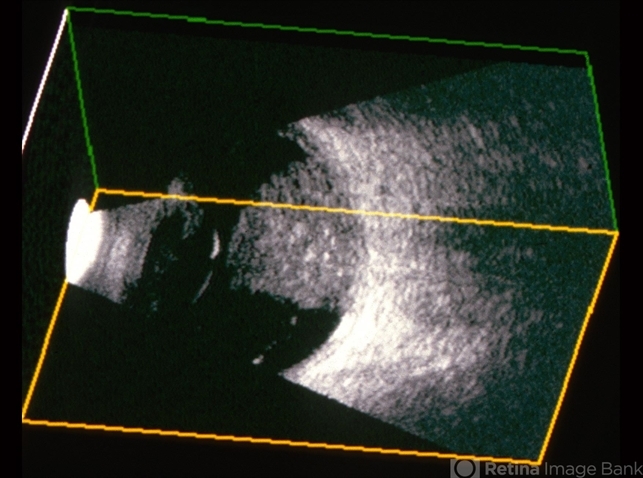

- B scan ultrasound, retinoblastoma

- B scan ultrasonography of the large endophytic retinoblastoma revealing internal hyper-reflective spots consistent with internal calcification.